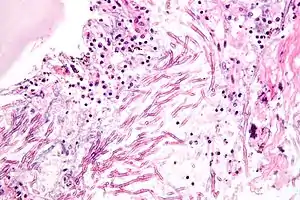

| تصویر میکروسکوپی از یک عفونت قارچی. افشانکچه (که شبیه اسپاگتی است) در مرکز تصویر دیده میشود. | |